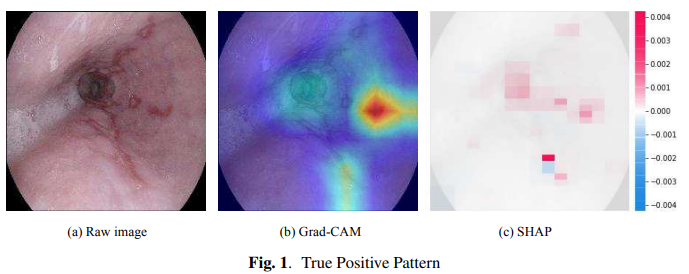

▌Deep-learning models in medical image analysis: Detection of esophagitis from the Kvasir Dataset

作者单位:同志社大学(日本)

论文链接:https://arxiv.org/abs/2301.02390

本研究旨在比较卷积神经网络模型(GoogLeNet、ResNet-50、MobileNet V2和MobileNet V3)在开放的Kvasir数据集的内窥镜图像中检测食管炎的准确性。结果显示,在这些模型中,GoogLeNet取得了最高的F1分数。根据真实阳性率的平均值,MobileNet V3比其他模型更有把握地预测食管炎。